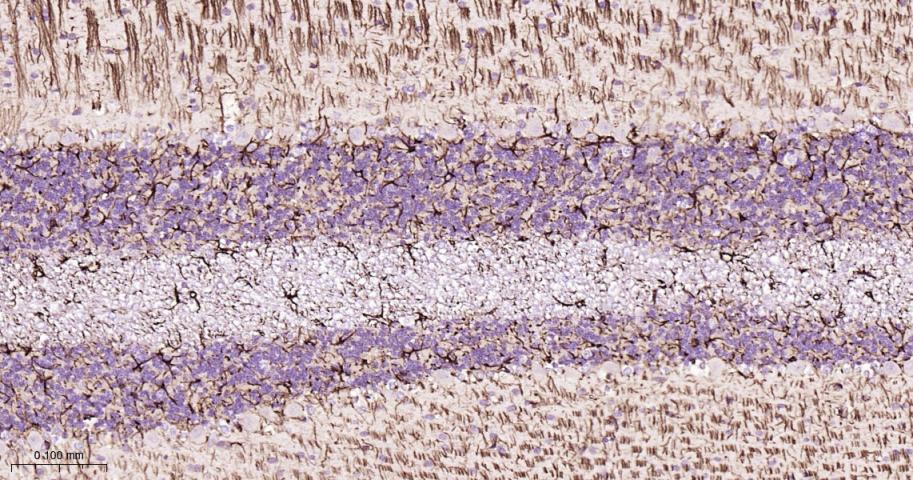

GFAP (Glial fibrillary acidic protein) is a member of the class III intermediate filament protein family. GFAP is heavily and specifically expressed in astrocytes and certain astroglia of the central nervous system, in satellite cells of peripheral ganglia, and in non-myelinating Schwann cells of peripheral nerves. In addition, neural stem cells strongly express GFAP. Antibodies to GFAP are very useful as markers of astrocytic cells. In addition, many types of brain tumor, presumably derived from astrocytic cells, heavily express GFAP. GFAP is also found in the lens epithelium, Kupffer cells of the liver, in some cells in salivary tumors and has been reported in erythrocytes. GFAP is used as a marker to distinguish astrocytes from other glial cells during development. Mutations in this gene cause Alexander disease, a rare disorder of astrocytes in the central nervous system. Alternative splicing of the GFAP gene results in multiple transcript variants encoding distinct isoforms.

*5. 发表论文时引用本产品的写作建议 "IHC0101R, Bioss Antibodies"。引用示例: “Rat tissue sections using Rat GFAP IHC Kit (IHC0101R, Bioss Antibodies) were stained for GFAP according to the manufacturer's instructions.”